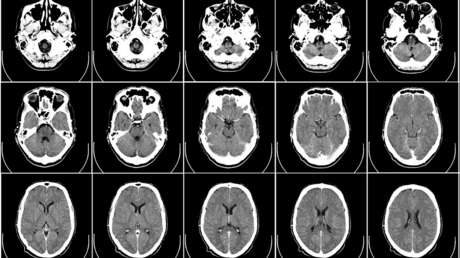

Cinco años después, Brian comparó las imágenes actuales de su cerebro con los escáneres cerebrales realizados cuando estaba pasando el curso de desintoxicación. Basándose en un método de evaluación de la edad cerebral a partir de la densidad de materia gris, Brian constató que había logrado rejuvenecer su cerebro en comparación con su estado anterior, de tal forma que su edad cerebral evaluada llegó a ser 10 años más joven que la cronológica, explica en su artículo para Medium.